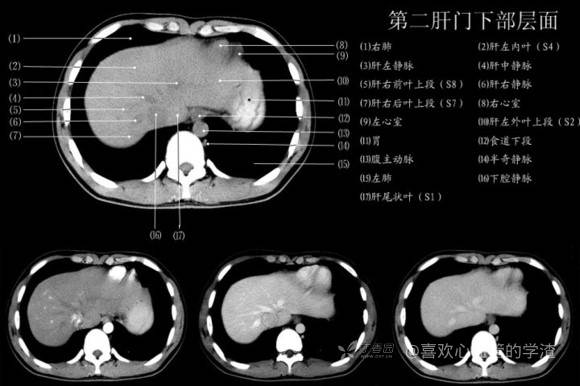

其实你离掌握上腹部 CT 影像只有一套高清实用图谱的距离,下面把我最喜欢的这本图谱分享给大家,为了方便阅读,我加了中文标识。后面附赠几张血管相对位置解剖关系图片,帮助大家理解(文中多图,建议在 wifi 环境下查看)。